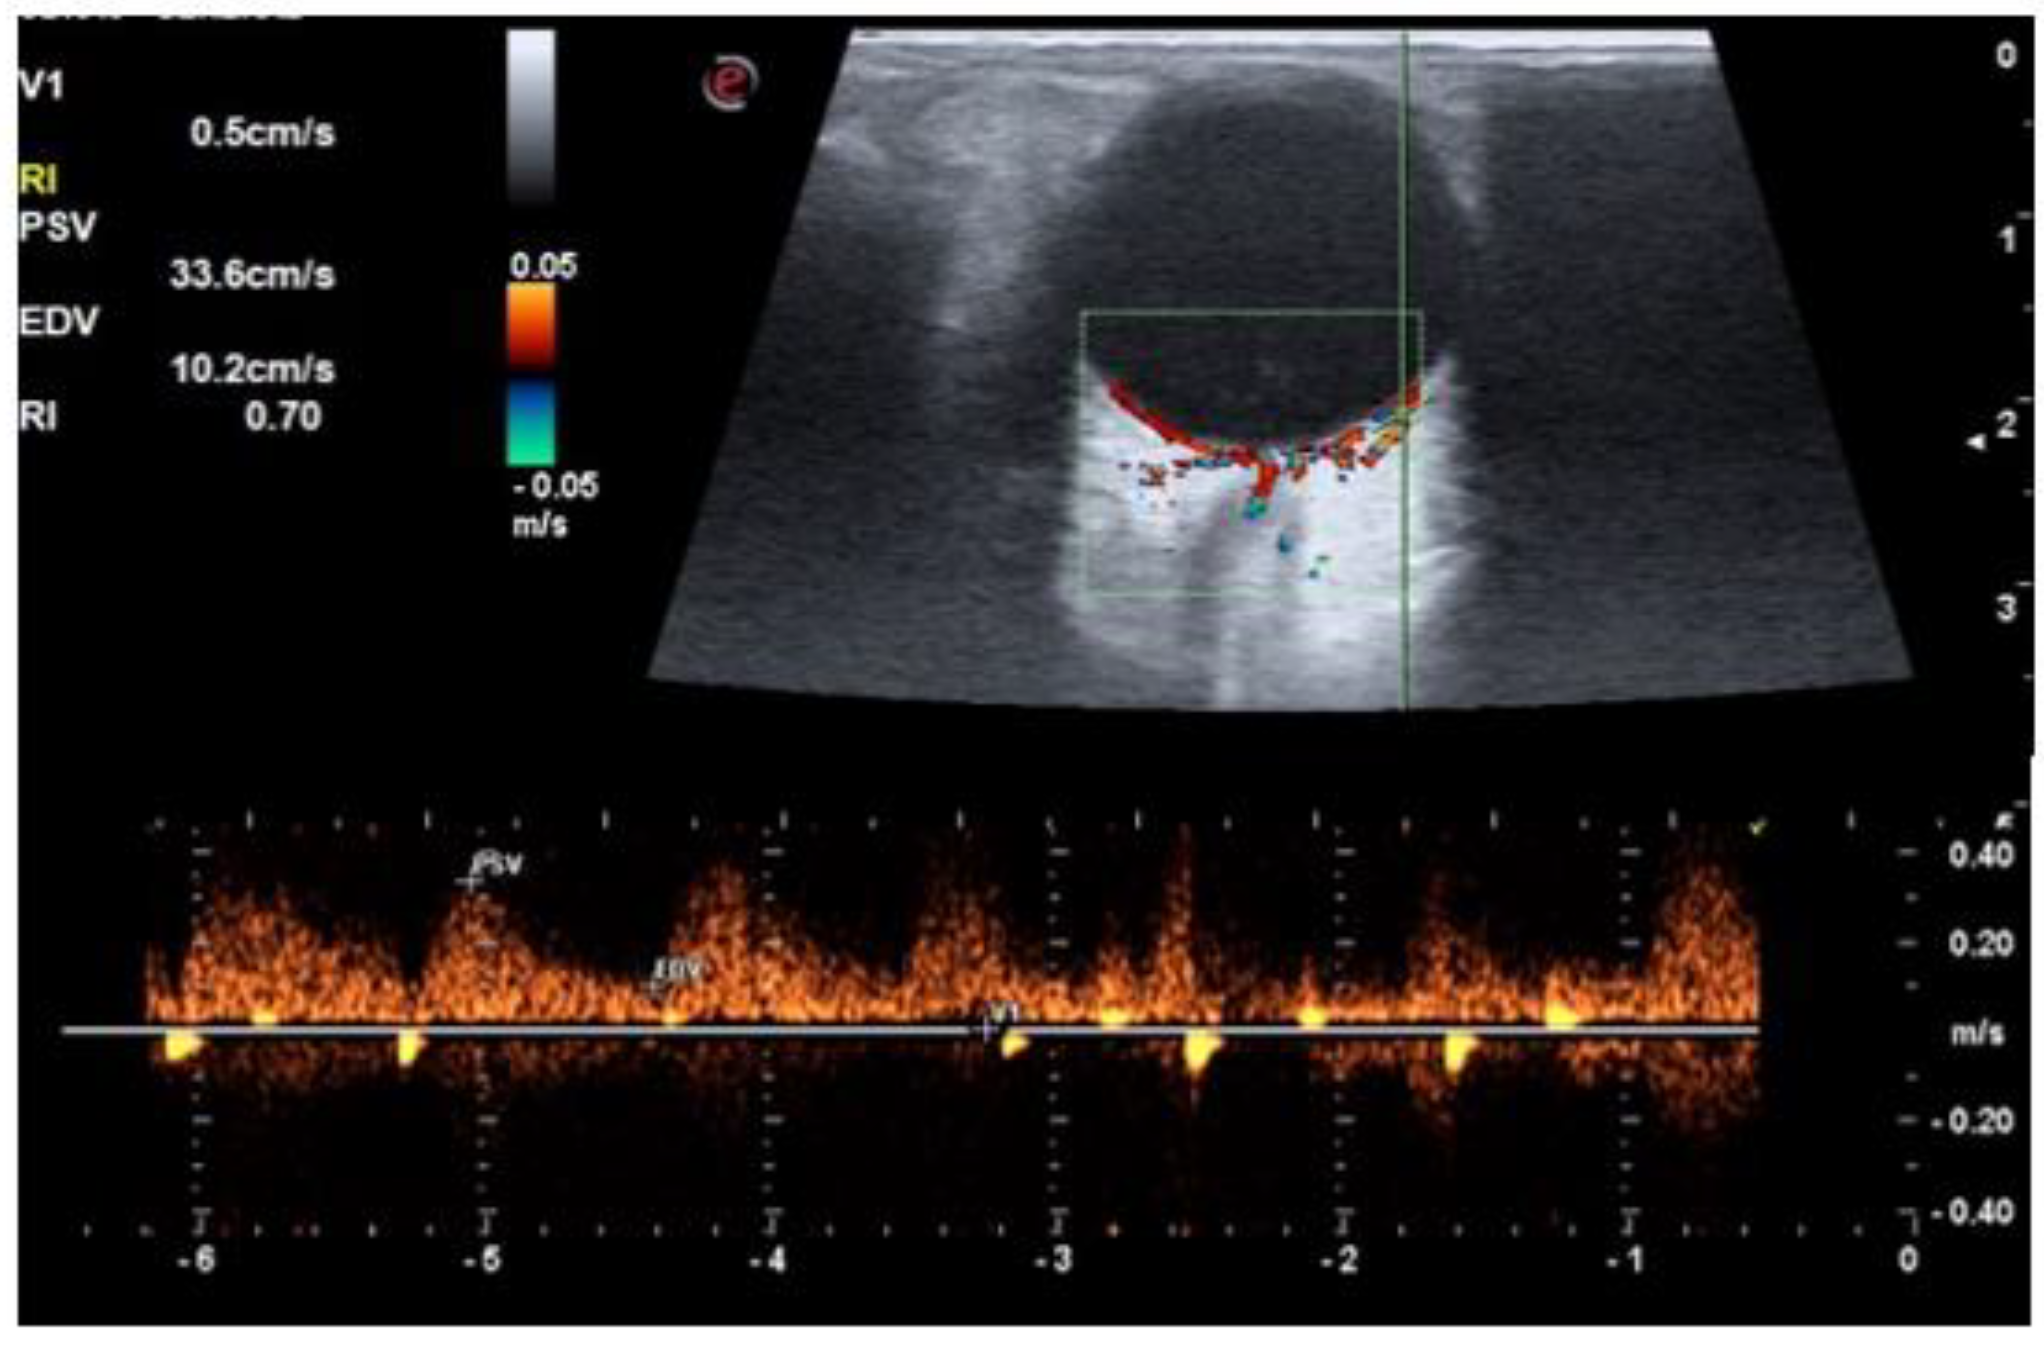

| PSV of ophthalmic artery (cm/s) | 31.9 ± 2.6 | 32.7 ± 3.0 | 33.8 ± 3.8 | 0.550 |

| EDV of ophthalmic artery (cm/s) | 8.7 ± 0.9 | 8.8 ± 1.6 | 8.3 ± 1.3 | 0.240 |

| RI of ophthalmic artery | 0.72 ± 0.02 | 0.73 ± 0.03 | 0.75 ± 0.03 | <0.001 |

| PSV of central retinal artery (cm/s) | 16.1 ± 1.9 | 15.8 ± 3.1 | 14.2 ± 2.7 | 0.010 |

| EDV of central retinal artery (cm/s) | 5.1 ± 0.7 | 4.8 ± 1.1 | 3.9 ± 1.0 | <0.001 |

| RI of central retinal artery | 0.68 ± 0.03 | 0.69 ± 0.03 | 0.72 ± 0.04 | <0.001 |

| PSV short posterior ciliary arteries (cm/s) | 19.1 ± 2.5 | 18.0 ± 4.2 | 16.7 ± 4.9 | 0.030 |

| EDV short posterior ciliary arteries (cm/s) | 5.9 ± 0.7 | 5.1 ± 1.3 | 4.3 ± 1.0 | <0.001 |

| RI short posterior ciliary arteries | 0.69 ± 0.03 | 0.71 ± 0.03 | 0.73 ± 0.5 | <0.001 |